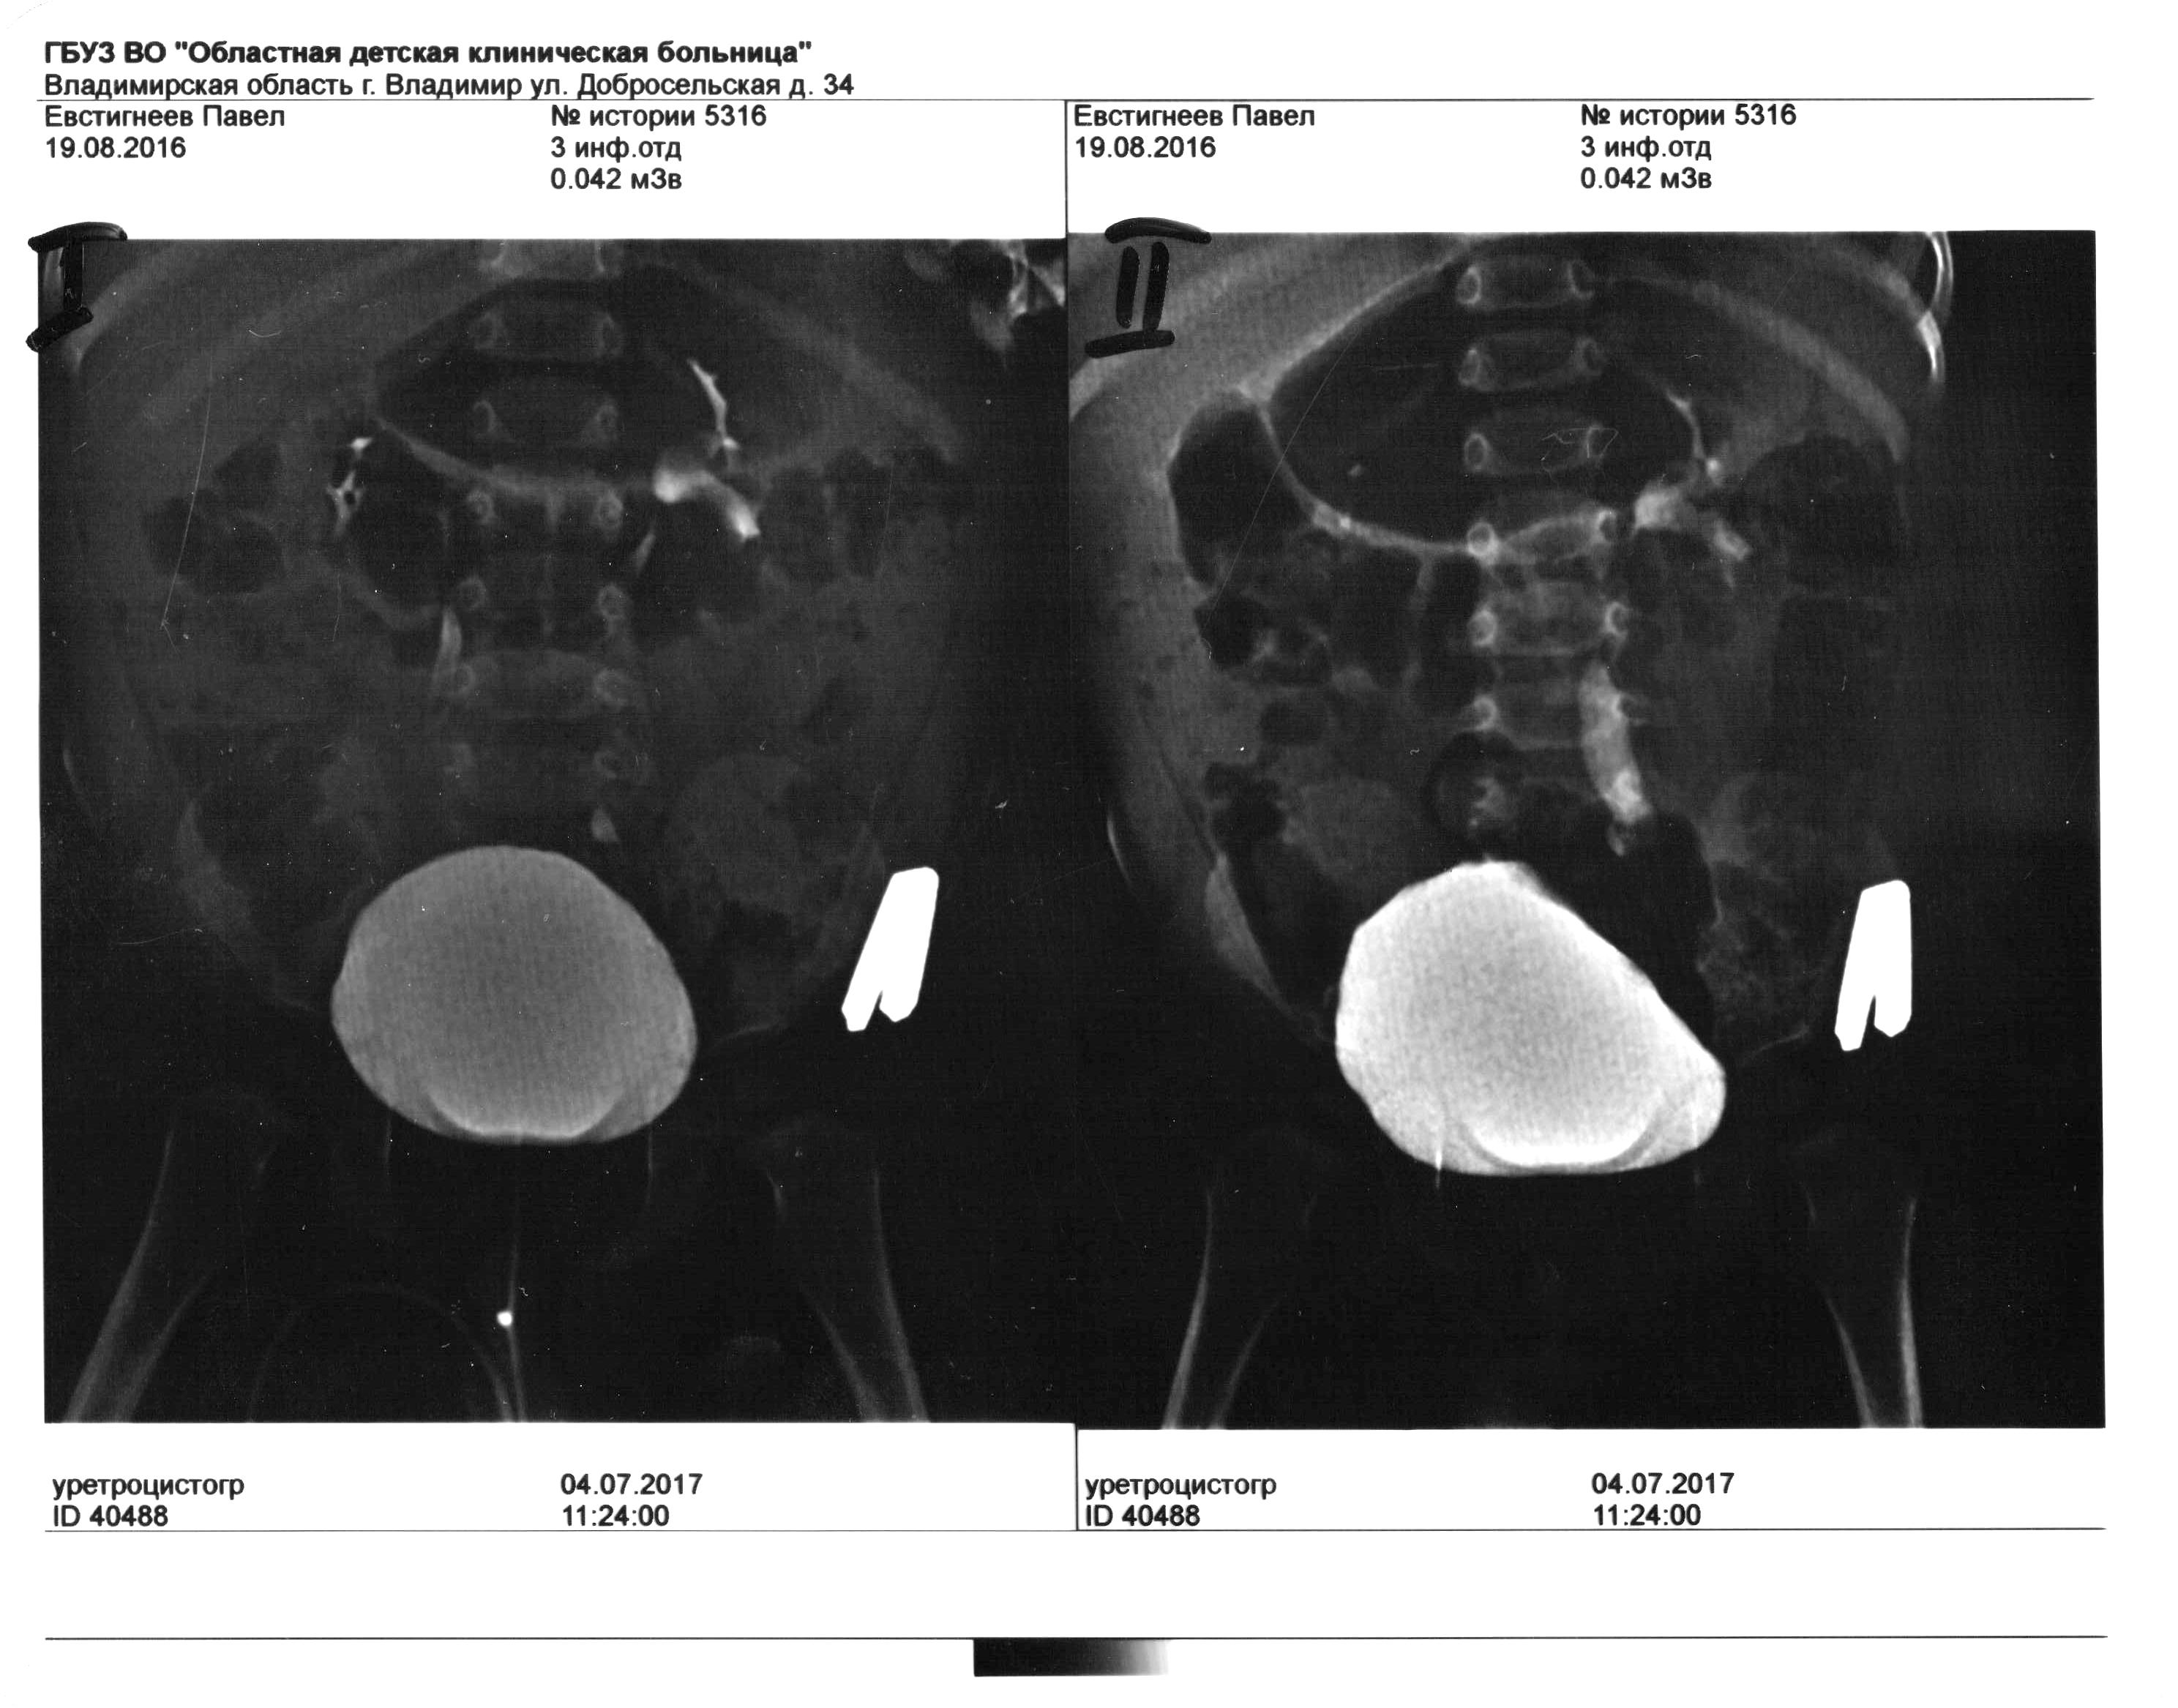

Сыну 1 год, постоянные пиелонефриты с 6 месяцев. Месяц назад обследовались в областной больнице г. Владимира. Диагноз:двухсторонний ПМР 2-3 степени, клапан задней уретры?. Клапан не могут посмотреть,нет оборудования. Пока носим катетер Фалея, но постоянно подскакивает температура под 40.

Прилагаю цистографию.